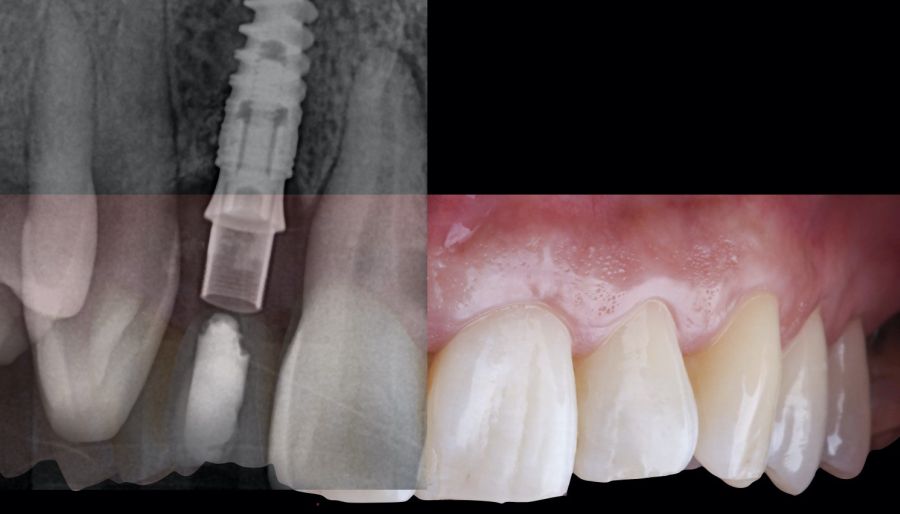

-Fase II: la cicatrización transcurrió sin complicaciones. Tras 5 meses de la cirugía de preservación alveolar, se planificó la cirugía implantológica guiada en posición 1.2 (Figura 2). Para ello, se utilizaron un archivo DICOM procedente de la tomografía computarizada de haz cónico (CBCT) y el archivo STL procedente del escaneado mediante un escáner óptico intraoral. Con esta información se construyó una férula quirúrgica de soporte dental (Figura 3). La férula quirúrgica se ancló sobre los dientes y guió la realización del lecho implantario y la colocación del implante. La técnica quirúrgica de cirugía guiada consistió en una cirugía con colgajo, preparando e insertando el implante (3,5 x 11,5 mm) según el protocolo estandarizado de cirugía guiada Nobel Active® (Nobel Biocare AB, Gothenburg, Sweden). Una vez colocado el implante 1.2, se obtuvo un injerto gingival compuesto de epitelio y tejido conectivo de la mucosa masticatoria palatina. A continuación, se realizó la desepitelización de la capa superficial de dicho injerto fuera de boca mediante una hoja de bisturí 15C con la finalidad de obtener un injerto de tejido conectivo de la capa subyacente18.

El injerto desepitelizado se insertó y posicionó por vestibular y oclusal mediante un punto colchonero horizontales utilizando sutura 5-0 no reabsorbible (Figura 4)19.

El resultado clínico final fue satisfactorio cumpliendo las demandas estéticas del paciente. Los tejidos blandos estaban morfológicamente y dimensionalmente estables sin ningún signo de inflamación. Sin embargo, los cambios del tejido blando periimplantario (espesor volumétrico vestibular) fueron demostrados de manera cualitativa y cuantitativa (Figuras 8 y 9). En el postoperatorio inmediato (T1), la ganancia media obtenida al comparar T0 frente a T1 fue de 0,88 ± 0,15 mm con un incremento máximo de 1,1 mm. Al comparar T0–T2, se observó una ganancia media de 0,73 ± 0,23 mm. Es decir, se ha producido una contracción de volumen de 0,16 mm desde la colocación del injerto (T1) hasta pasado un mes y medio (T2).